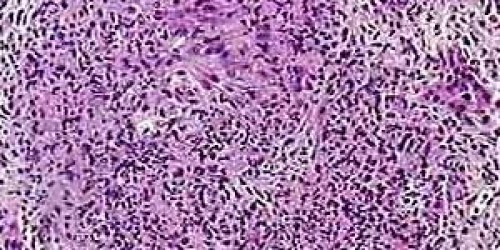

I have been diagnosed with Wegener’s granulomatosis couple of years ago, but since it was discovered early, it all ended well. My kidneys are also ok, so there was no need for transplantation. Since I have a 15 year old daughter, I would like to know at what age this disease can appear.

There is no exact age group for this condition, although, usually older people are affected. And unfortunately, the cause is still not determined. Although it has been found out that use of drugs might induce occurring of some secondary form of this illness. The good thing is that if it is discovered early and treated properly, the patient might expect a full recovery. As it happened to you.